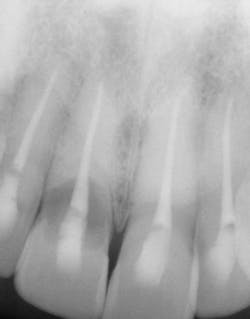

Figure 1: An X-ray revealed severe root resorption on No. 8.

A periapical of tooth No. 8 revealed my worst fears (see Figure 1). As a hygienist, as a woman, as a person who truly cares about health as well as appearance, I was devastated. Tooth No. 8 had completely failed and the root was resorbed to the point of complete instability. Everything I had been feeling and dreading the last three months was now out in the open on a giant screen in front of me. It was gaping damage and terminal.